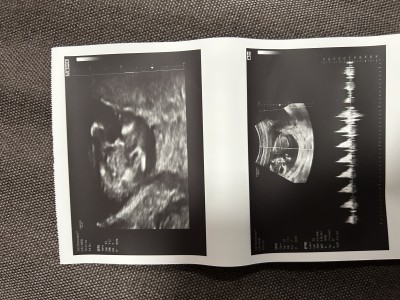

Ultrason kâğıdından anlayan var mı acaba rica etsem yorumlar mısınız

Gebelik haftası 13+6

Cinsiyeti erkek hayırlı olsun ben öyle gördüm

Çok teşekkür Allah razı olsun 11 haftalıkken tahminim erkek dedi bugün kontrolüm vardı yüzüstü durduğu için net göremedi bacak arasında bişey göremiyorum kıza benziyor 18. Haftada kontrol ederiz belli olur dedi

Benim oğlumda 11 haftalıkken bu şekilde şimdi 27 haftalıgız hep erkek dedi doktor sizinde erkek hayırlı olsun